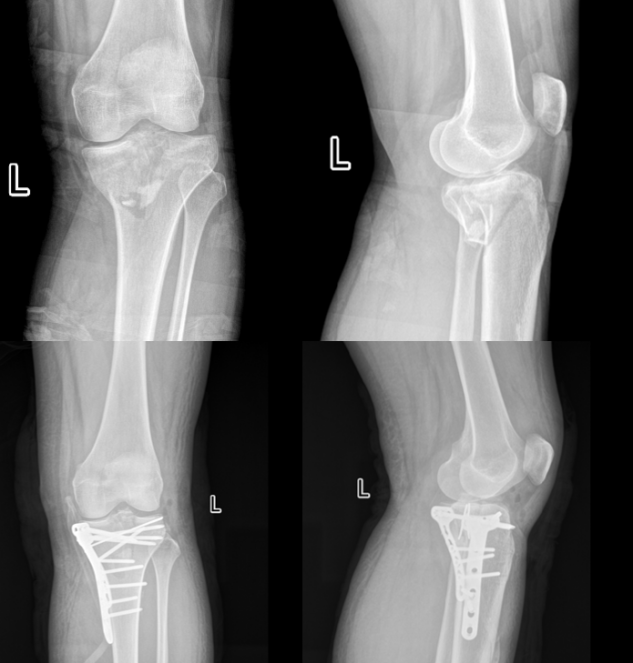

胫骨平台骨折